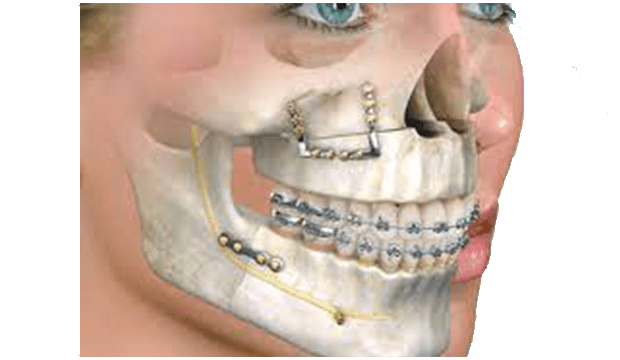

Çene cerrahı, çene kemiklerinde kesiler (osteotomi) yaparak çeneleri doğru pozisyona getirir. Çene hareketiniz tamamlandıktan sonra, kemikleri yeni (planlanan) konumlarına sabitlemek için kemik plakaları, vidalar, teller ve lastik bantlar kullanılır. Diş teli için kullanılan bir braketten daha küçük olan bu vidalar zamanla kemik yapısına entegre (kaynaşma) olurlar.

Bazı durumlarda çenelere fazladan kemik ekleme ihtiyacı olabilir. Bu durumda genellikle iliak adı verilen ön kalça kemiği bölgesinden kemik alınarak gerekli bölgeye plaklar ve vidalarla sabitlenir.